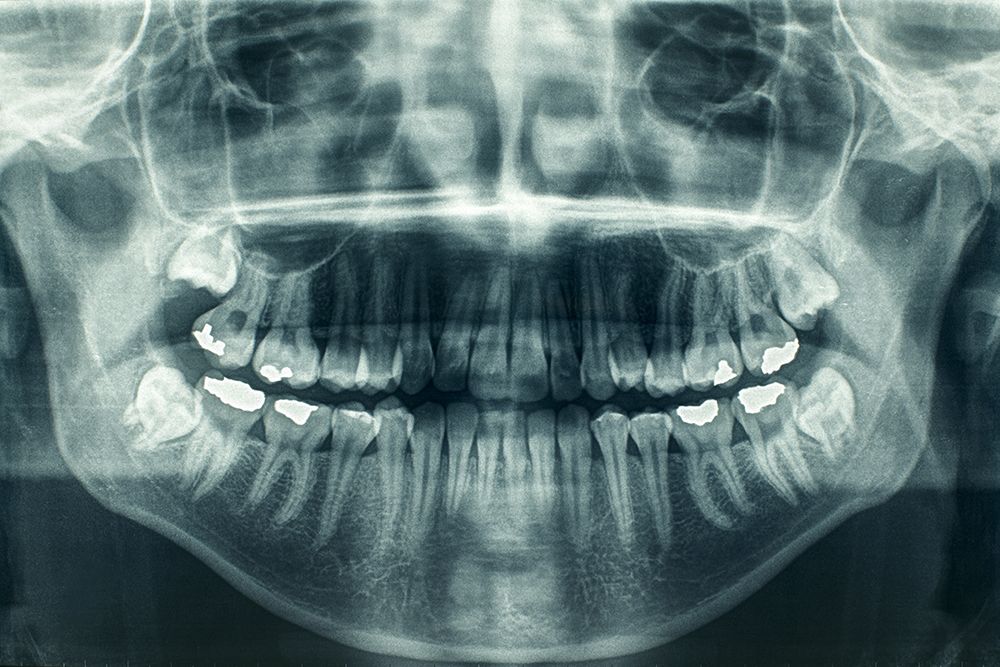

En Chile, el 81 por ciento de los adultos mayores tiene menos de 20 dientes. La enfermedad más frecuente es el daño periodontal y un 57 por ciento tiene caries.

De este grupo etario, el 81 por ciento tiene menos de 20 dientes. La enfermedad más frecuente es el daño periodontal, un 57 por ciento tiene caries y los problemas bucales que se presentan, se relacionan con la diabetes, enfermedades cardiovasculares, de salud mental, de comunicación oral y estética. Las políticas existentes, hoy se enfocan Garantías Explícitas en Salud de urgencia odontológica, el de atención integral del adulto de 60 años y el programa de reforzamiento.